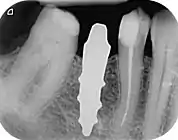

X-ray of root analogue dental implant single rooted right lower second premolar